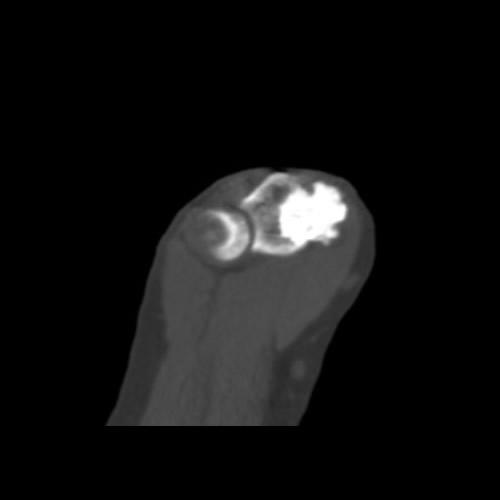

Mayo 2024. Hospital Italiano Paciente de sexo femenino de 37 años de edad, la cual refiere dolor en codo.